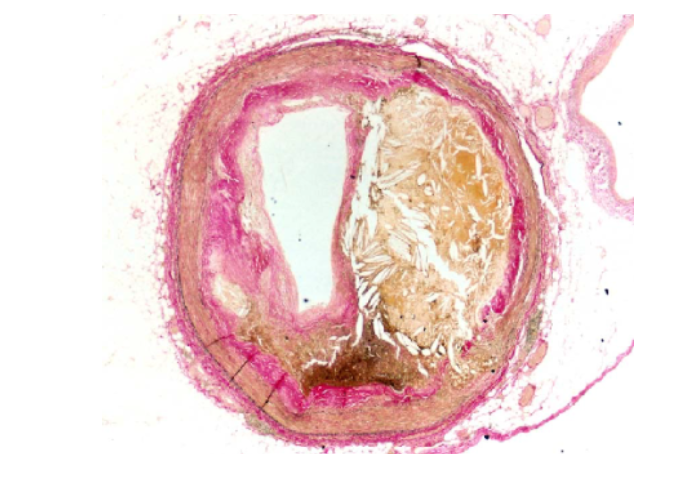

Атеросклеротическая бляшка аорты

Атеросклеротическая бляшка аорты 69 фотографий